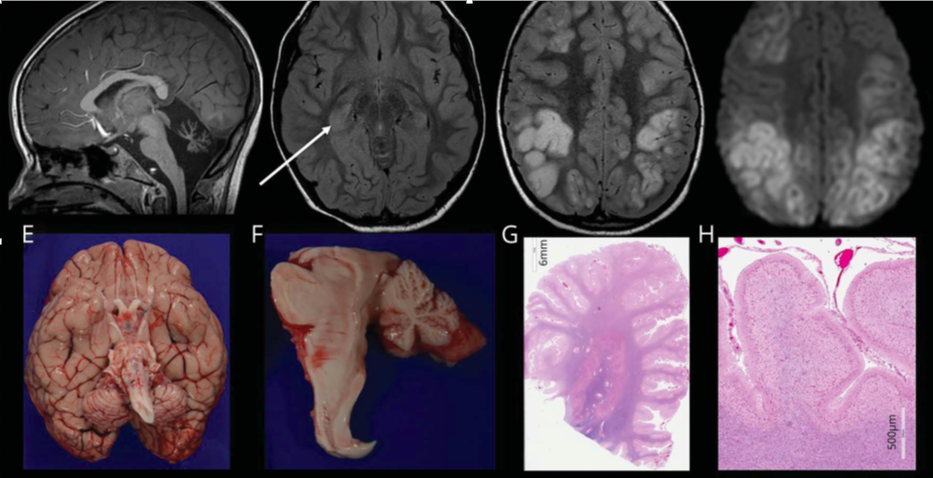

图 严重的CACNA1A基因相关疾病的神经影像学和组织病理学特征 (A–D) 5岁时入院第2天(A,B)和第10天(C,D)的脑MRI。(A) 矢状位T1图像提示小脑蚓部萎缩;(B)轴位FLAIR图像提示右侧海马信号增强、体积增大(箭头);(C)轴位FLAIR序列提示皮质高信号;(D)轴位DWI序列提示皮质多处弥散受限,以额顶部为主(未显示相应的表观扩散系数图)。(E-H)神经病理学结果。(E)大脑大体图像显示小脑和脑干偏小;(F)脑干和小脑的中矢状切面突出了蚓部和小脑半球偏小;(G)整个小脑半球提示脑叶萎缩;(H)在高倍镜下显示小脑叶已经完全丧失浦肯野细胞和外部颗粒细胞层并伴有胶质增生。

死亡后进行脑活检和神经病理学检查(图E-H)。小脑蚓部和半球萎缩,脑干内无其他病灶。浦肯野细胞完全丧失。右侧枕叶可见累及大脑皮质的出血性病变。